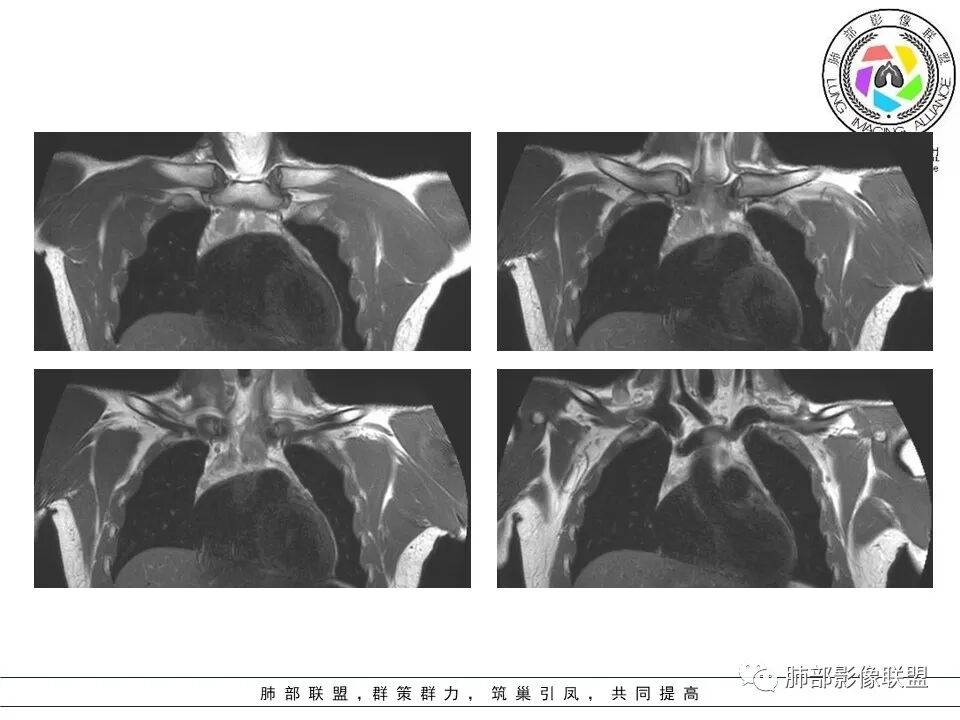

孙老师发一下冠状位

多个病灶

孙海峰:

问题是不是都是结节状,部分是条带状

胸腺内的

多发病灶